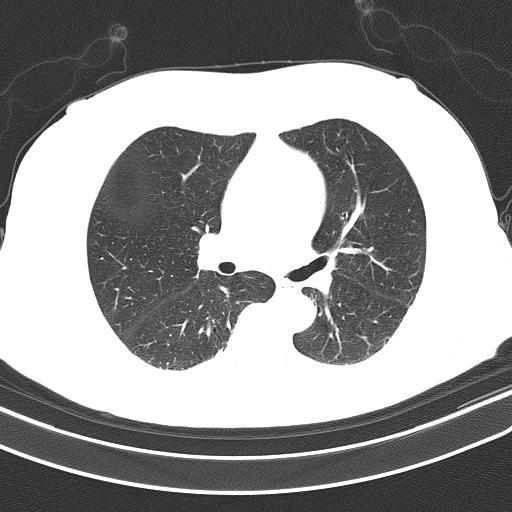

The problem is the segmented lung still contains white borderers like this:

Segmented lung (output):

segmented lung

Unsegmented lung (input):

unsegmented lung